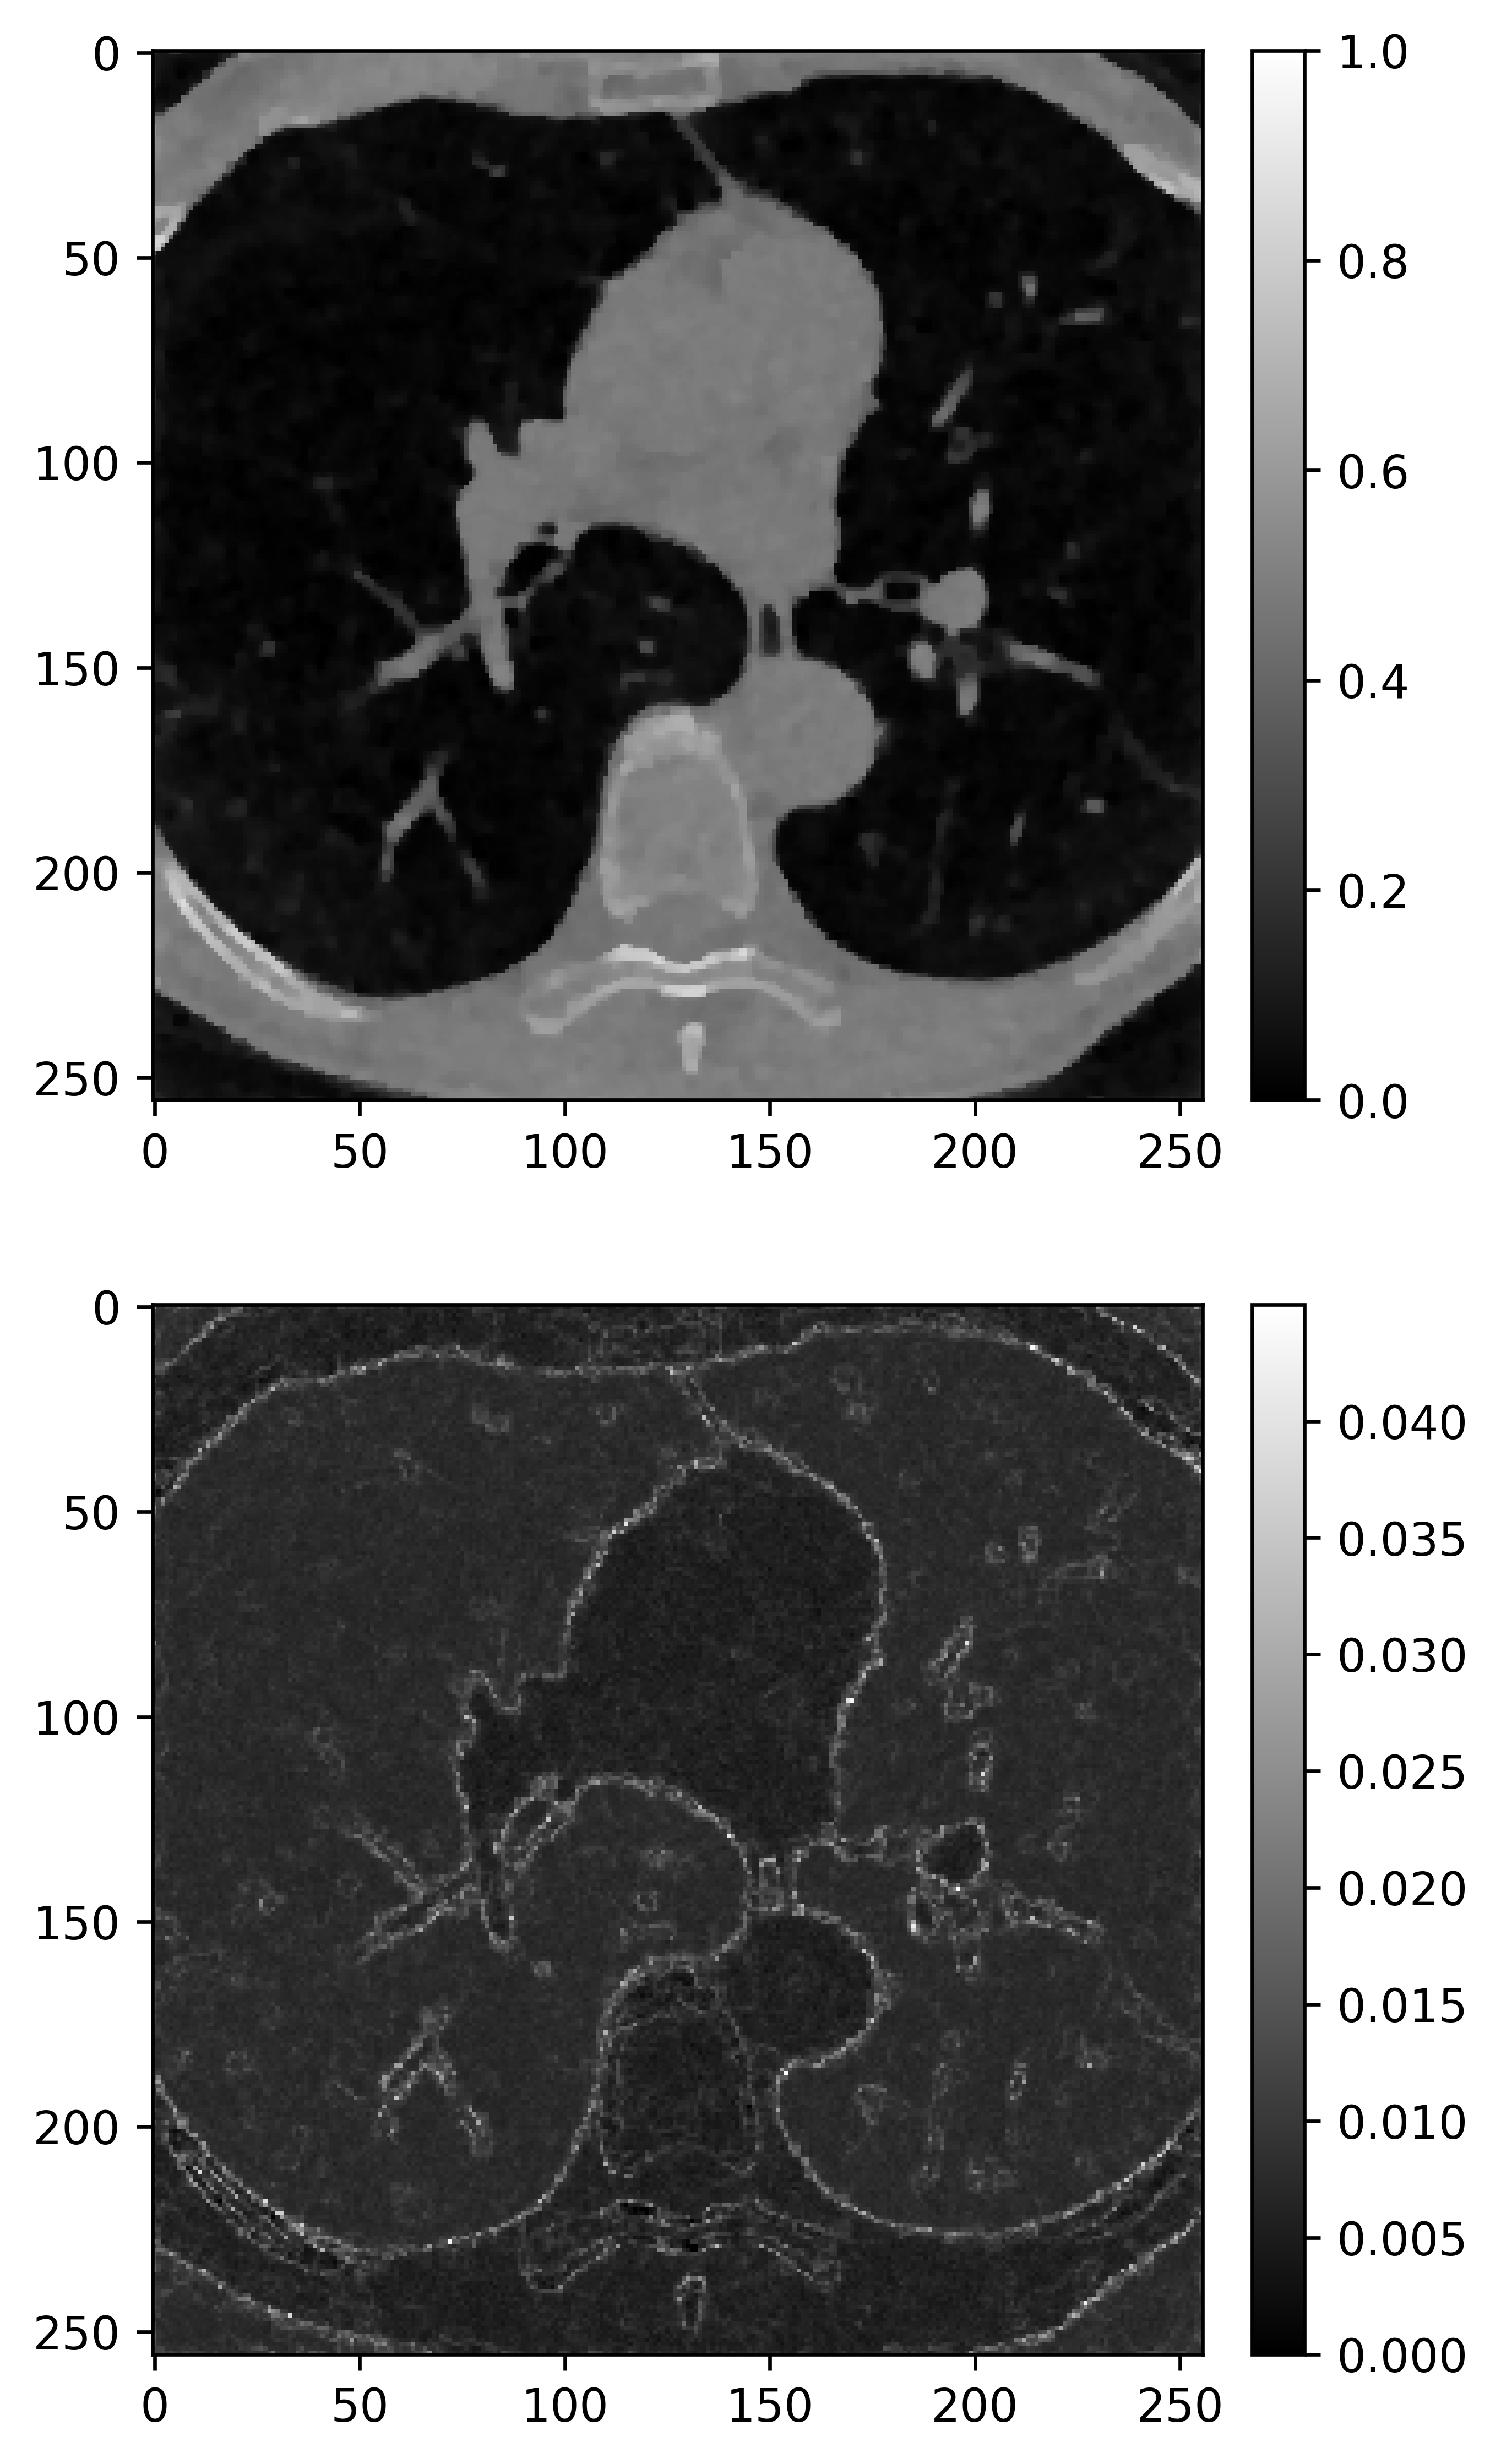

Figure 4: Comparison of CT reconstruction for Shepp–Logan phantom with different priors. The upper images are posterior mean. The bottom images are posterior standard deviations.

Refer to caption

(a) Gibbs-BPS

(b) Gibbs

(c) PLD

(d) pCN

Figure 5: Comparison of CT reconstruction for grains phantom with different priors. The upper images are posterior mean. The bottom images are posterior standard deviation.

The posterior mean and posterior standard deviation are shown in Figure 4 and Figure 5. Overall, for two small scale image problems, the fused L1/2L_{1/2} prior and the fused horseshoe prior have comparable performances in terms of both PSNR and SSIM. The images recovered by Total variation Gaussian prior always has the worst quality. The fused LASSO prior works reasonably well in Shepp–logan phantom. The main performance difference among all the algorithms is in Grains phantom, both the fused LASSO prior and the TV-Gaussian prior significantly fall behind. The fused L1/2L_{1/2} prior allows us to obtain a sharper reconstruction in Grains phantom, despite some of the grain features missing in the reconstruction and its PSNR is slightly lower than the fused horseshoe prior.

For uncertainty quantification, we observe that, all the posterior standard deviations are relatively large at the edge locations and almost zero in the rest of the image. Among all these priors, the posterior standard deviations based on the fused LASSO prior are particularly small in these two cases.